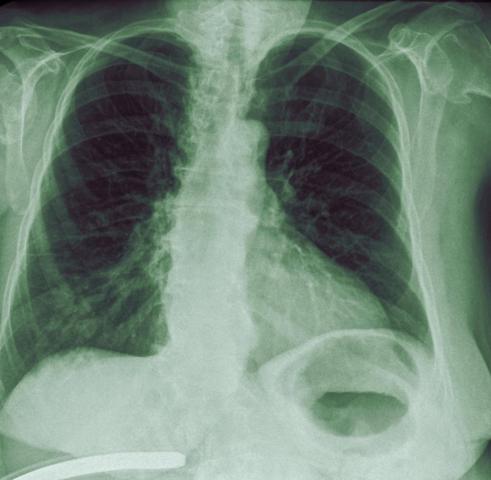

Sauerstoffsättigung bei Lungenentzündung

Die Sauerstoffsättigung bei einer Lungenentzündung kann stark variieren, abhängig von der Schwere der Erkrankung und dem individuellen Zustand des Patienten. In schweren Fällen kann die Sauerstoffsättigung deutlich absinken, da die entzündeten Lungenbläschen nicht mehr ausreichend Sauerstoff ins Blut abgeben können. Dies kann zu Atemnot und einer bläulichen Verfärbung der Haut führen.

Eine niedrige Sauerstoffsättigung ist ein Zeichen für eine schwere Lungenentzündung und erfordert eine sofortige ärztliche Behandlung. Im Krankenhaus wird die Sauerstoffsättigung regelmäßig überwacht und gegebenenfalls mit zusätzlichem Sauerstoff unterstützt, um den Körper ausreichend mit Sauerstoff zu versorgen.

Es ist wichtig zu beachten, dass die Sauerstoffsättigung allein kein Maßstab für die Schwere der Lungenentzündung ist. Weitere Symptome und Untersuchungen wie Röntgenbilder oder Blutuntersuchungen sind ebenfalls entscheidend für die Diagnose und Behandlung der Erkrankung.

Wie hoch ist die Sauerstoffsättigung bei Lungenentzündung?

Bei einer Lungenentzündung kann die Sauerstoffsättigung im Blut abfallen. Ein normaler Wert liegt in der Regel zwischen 95% und 100%. Bei einer Lungenentzündung kann die Sauerstoffsättigung unter diesen Bereich fallen, was auf eine eingeschränkte Aufnahme von Sauerstoff hinweist.